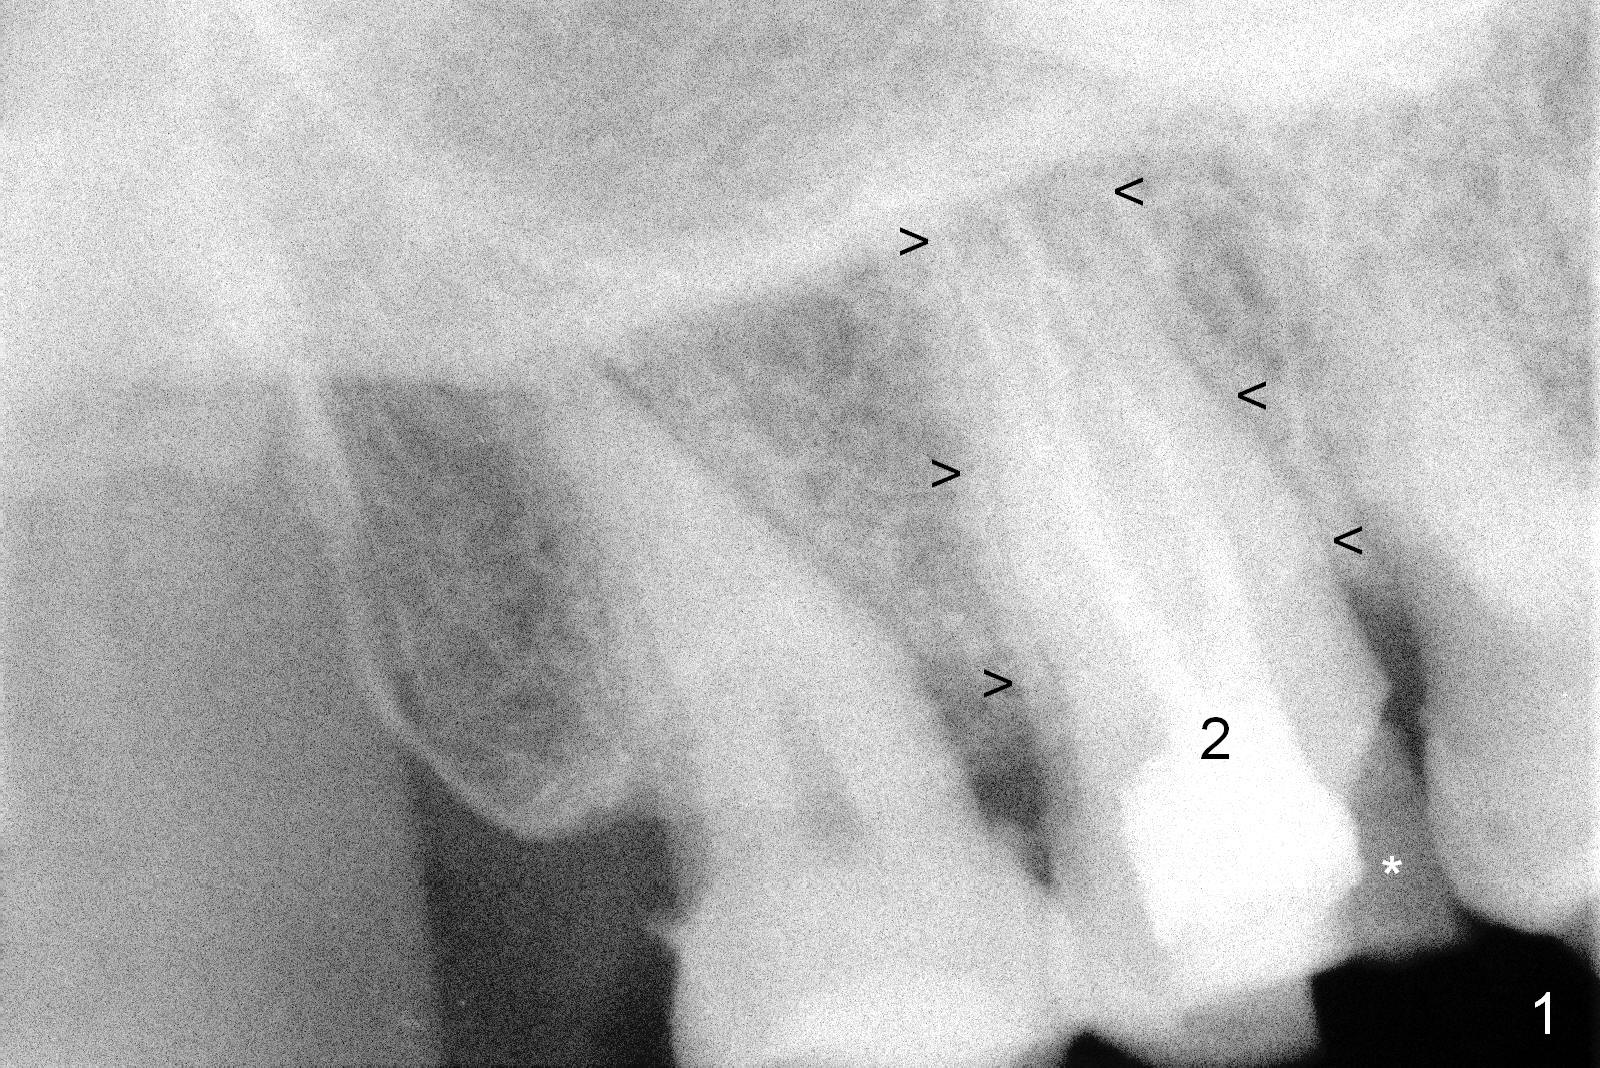

A 65-year-old lady is at early stage of Parkinson's disease and appears to be a bruxer. There are multiple chipped teeth, including #2 (Fig.1,4 *). She chooses implant over RCT retreat. A tissue-level implant (Fig.2) matches the root shape of the affected tooth better than a bone-level one (Fig.3), because of taper. The buccopalatal and mesiodistal dimensions of the extraction socket are 11 and 8 mm, respectively (Fig.5,7).

The buccal roots are fused. The buccal socket (BS) seems to be larger than the palatal one (PS). There is a septum (S) between the 2 sockets. Both the buccal and palatal plates (BP, PP) are intact. The anatomy is illustrated in Fig.6a (buccopalatal section) with the same abbreviations, mentioned above. SF: sinus floor.